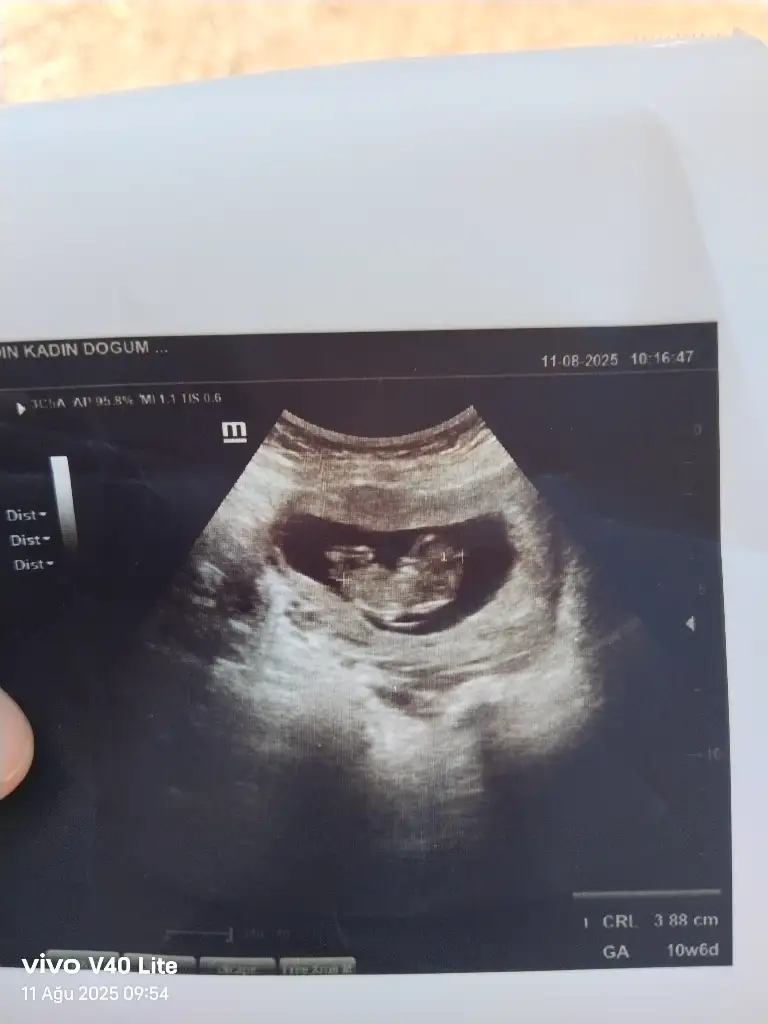

Merhaba benimde yorumlarmisiniz rica etsem 11+1Bariz erkek görüyorum, sağlıcakla gelsin inşallah![]()

Kız gördüm sanki, sağlıcakla gelsinArkadaşlar 12+5 ultrason fotoğraf ı kız mı erkek mı sızce

Bir çoğunda ölçüm çizgisi o kısıma denk gelmiş ama, bir tanesinde kız gördüm sanırım, sağlıcakla gelsinMerhaba benimde yorumlarmisiniz rica etsem 11+1

Ben de kız gördüm ama annenin içine doğan da olabiliyor çoğunlukla, hayırlısıyla sağ salim doğsunlar inşallahAllah razı olsun cnm benim bunu erkek bekliyordum kısmetİKİZLER normalde çif yumurta ikizi diğeri kesin kız dedi buna da kız gıbı küçük daha dedı belli olmuyor dedı belki siz tahmin edersiniz cinsiyeti dıye atmak istedim size kıza benzıyor dedı erkek hissediyorum ama ben ya kısmet

Aaa çok sağolun ben hiç anlamıyorum Instagram da 5 kişiye sordum 4 kız dedi 1 erkek teoriye ve boyama işlemi ile bakanlar da oldu gönlümden geçen kız umarım doğrudur gördüğünüz ben anlamıyorum . Rica edecem eğer sizi yormayacaksam nerde gördünüz hangi fotoğraf da acbaBir çoğunda ölçüm çizgisi o kısıma denk gelmiş ama, bir tanesinde kız gördüm sanırım, sağlıcakla gelsin

Bakın işte burada 3 çizgiMerhaba benimde yorumlarmisiniz rica etsem 11+1

Çok teşekkür ediyorum sağolunBakın işte burada 3 çizgiAma henüz yeni yeni oluştuğu için yanılma payı olabiliyor tabiki

Sizce benim nedir 11+1Erkek bence

Kesesini erkeğe benzettim sağlıkla gelsinSizce benim nedir 11+1